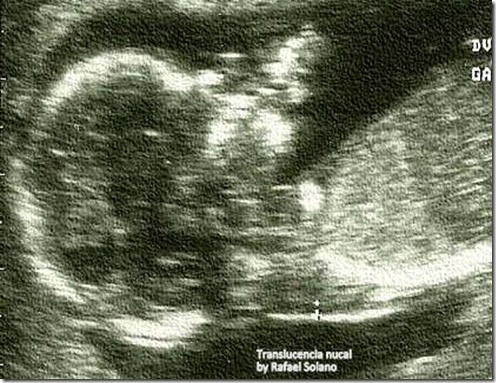

El equipo del Dr. Rafael Solano les desea: